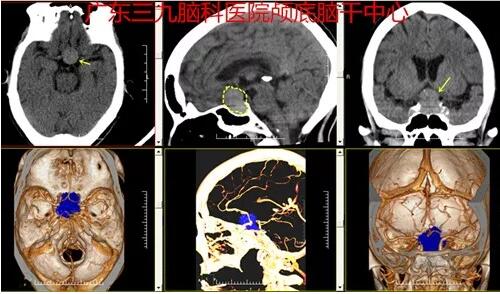

图1:头颅CT、CTA检查示鞍区占位性病变内示少许细小血管影,病变紧贴Willis环前部,双侧颈内动脉未见包绕。